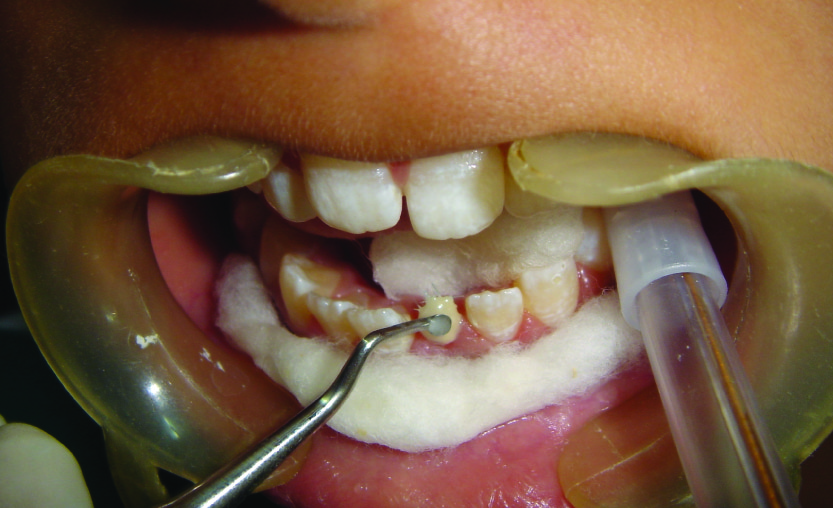

A 12-year-old female patient visited the Department of Pediatric Dentistry with a complain of broken left lower front tooth since four months. The patient did not complain of any pain [Table/Fig-1]. The parent of the patient told that the girl had a fall two years back in which the lower front tooth got broken. There was pain and tenderness reported at that time and they had visited a dentist for the same. On further enquiry it was revealed that the mentioned tooth had been root canal treated six months back and restored but the restoration came out within a month. The re-restoration also did not last more than 15 days. On examination lower left central incisor was fractured and there was neither pain reported nor tenderness to percussion. The tooth structure was less for a composite make-up or a crown. After thorough examination it was decided to go for a post and core and composite make up. As it was an anterior tooth in a young patient it was decided to go for fibre-reinforced composite (Ribbond, Ribbond THM, Ribbond inc.Seattle,WA) as post and core material as it is esthetic and has adequate strength. As the tooth was adequately obturated [Table/Fig-2], preparation of the canal space was done [Table/Fig-3,4]. The use of ribbond does not require additional tooth preparation as is required for metal posts. The remaining tooth structure being less, rubber dam isolation could not be accomplished and we decided for high suction evacuation with cotton rolls to be suitable for isolation. Gutta percha was removed using gutta percha solvent until the desired length for post was achieved. The post hole was shaped using Gates Glidden drills (Roydent, West Palm Beach, FL), cleaned with 5% sodium hypochlorite and dried. The width of Ribbond is to be decided on the root canal space available. The depth of the post space was measured using a periodontal probe, and a 3-mm-wide Ribbond was cut using special scissors provided with the kit (Ribbond starter kit, Ribbond THM, Seattle), measuring twice the depth of the post space and 3–4 times the height of the core build-up [Table/Fig-5] and placed in dual cure adhesive resin and set aside in light protected container. The root canal wall was etched, washed thoroughly and then air-dried gently. Excess water was removed from the post space using paper points . The dual cure adhesive resin (Ed Primer II A&B) was applied using a microbrush and gently air-dried to evaporate the solvent. Dual cure resin cement was then placed inside the canal space. The Ribbond was removed from the resin and the excess resin was removed using a hand instrument [Table/Fig-6], folded in a V-shape and coated with dual-curing resin cement (Panavia, Kuraray Medical Inc., Japan). The piece of ribbond was then placed in the post space in a labial-lingual direction with a periodontal probe [Table/Fig-7]. Excess resin cement was removed, and the cement was cured for 20 s. The two protruding ends of the Ribbond strips formed the reinforcement for the core build up to replace the lost coronal portion of the tooth. The remaining resin mix from the syringe was extruded onto this framework to create a core resembling almost like the shape of a lower central incisor. The space between the protruding ribbon ends was filled with resin so as not to leave any voids. Composite resin was also placed so as to cover the ribbon ends completely and leave none of them exposed on the outer surface of the core. All the material was thoroughly light cured to create a set surface. The material was left in the mouth for a couple of hours to ensure complete set of the self curing component of the resin mix. The result of this procedure came out to be a single piece post and core, which was bonded onto the root, creating a solid structure without any wedging effect on the root. Moreover, the resin conforming to the inside shape of the canal space ensured no voids and eliminated “fitting” problems normally associated with cast posts. The bands of Ribbond reinforced the resin material and made it extremely strong and durable. Bonding of the entire material also created a single block of post and core, which is the essence sought for favourable occlusal force transmission and for resistance against debonding of the entire unit. The best thing was, there was no metal to mask with the crown since the base shade of the composite was a close enough match to the tooth and was translucent. These strips, although opaque, were white in colour and after being completely encased in the composite, were not visible. However, they did not contribute to the colour of the core in any adverse way. The restorative procedure was completed by building up the tooth using dual cure hybrid composite resin following technique of small progressive build up without any matrix [Table/Fig-8,9]. All these increments were fully light cured. Finishing and polishing procedures were performed using composite contouring and polishing discs. The patient was advised for a crown at a later stage after complete development of occlusion. The patient has been under follow up for two years now with six month follow up intervals and the restoration is still in good condition [Table/Fig-10,11]. As because the occlusion is not yet established we have decided to give crown on a later date.

Ribbond prepared to be inserted in canal